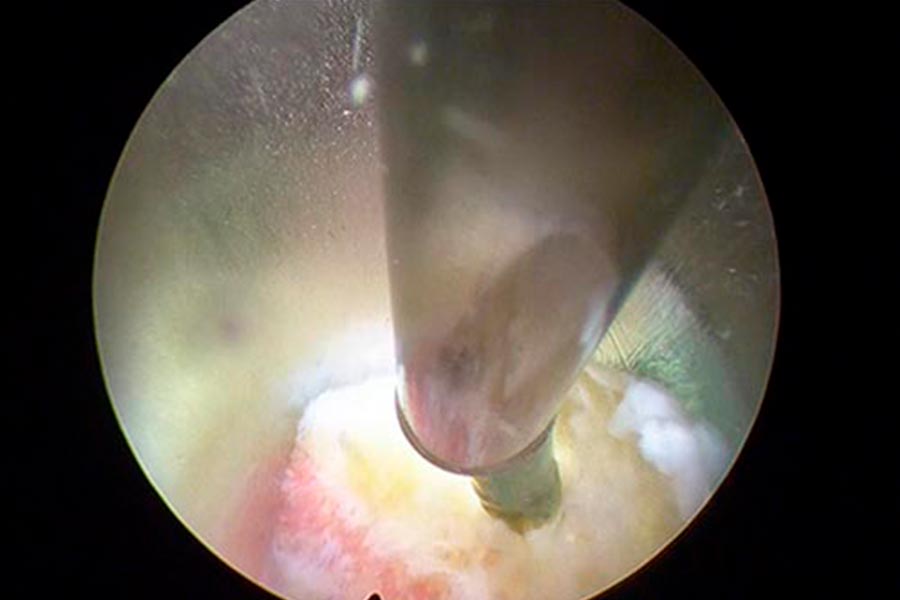

Caso clínico: endoscopia de columna multinivel L4L5 y L5S1

Durante la intervención quirúrgica, se abordarán los dos niveles mediante la técnica de endoscopia de columna.